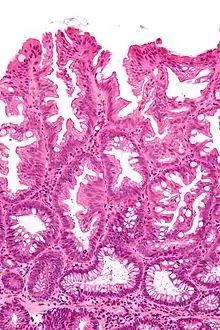

Sessile serrated adenoma

Sessile serrated adenomas are characterized by (1) basal dilation of the crypts, (2) basal crypt serration, (3) crypts that run horizontal to the basement membrane (horizontal crypts), and (4) crypt branching. The most common of these features is basal dilation of the crypts.